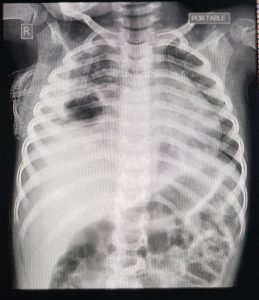

1 yr old baby is admitted with fever 3 days cough 2 days and breathlessness one day. She was feeding well ,but today became more dyspneic and was not feeding well

O/e. Rr 60/Mt,spo2 90%,hr 138/Mt,

temp 102 f

Dx: severe pneumonia

The diagnosis can be confirmed by Doppler ultrasonography, chest radiograph (which demonstrates a radiolucent lesion) ( image 1), or contrast-enhanced computed tomography (CT) ( image 3) if the diagnosis remains uncertain [133,134].

The diagnosis is suggested by a chest radiograph demonstrating a thick-walled cavity with an air-fluid level ( image 1) [40] and confirmed by contrast-enhanced CT in questionable clinical situations or if necessary before invasive interventions (eg, percutaneous aspiration, placement of a drainage catheter) [133]. Lung abscess is often accompanied by parapneumonic effusion [139,140].